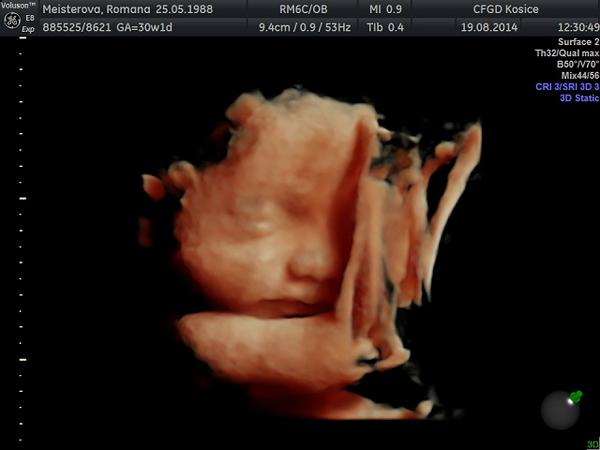

@5romanna5 a to morfo sono sa robi aj okolo toho 30tt, ze? chcela by som nan ist niekde, kde sa budu dat drobcekovia pozriet aj tym 3D, lebo muzik na samotne 3D odmieta ist, ze naco. nam ich na poradni meria teraz uz podla hlaviciek, bruska a stehennej kosti, ale nepovedal nam nic